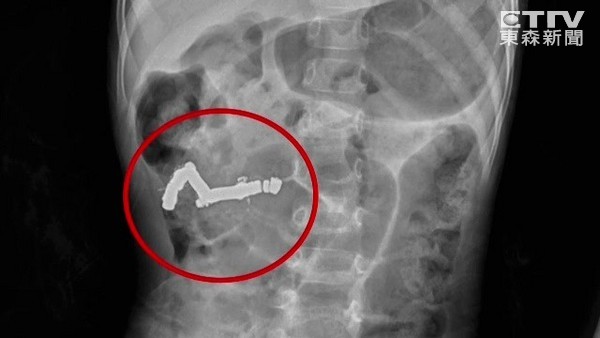

▲4歲童吞20顆磁石腸道打結,經開刀保命。

王小弟8月間感冒,父親到藥局買磁力貼布想幫他緩解症狀,未料他扯掉磁石吞下肚;從X光片左下角處很明顯看出長長一條異物,頭端成彎曲形狀,王小弟因此被折騰得哇哇大哭。

這一串一顆顆如鈕扣般的磁石,被男童當成巧克力糖吞下肚,因為吸力讓腸道打結、糾成一團,經手術取出後,近20顆黏在一起的磁石長約5.7公分(2英寸)。